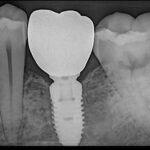

Single dental Implant

Single tooth implant most common procedure in dental practice fir single missing tooth. We ensure high quality dental Implant with high success rate. Treatment time 3 to 6 months.

Implant Gallery